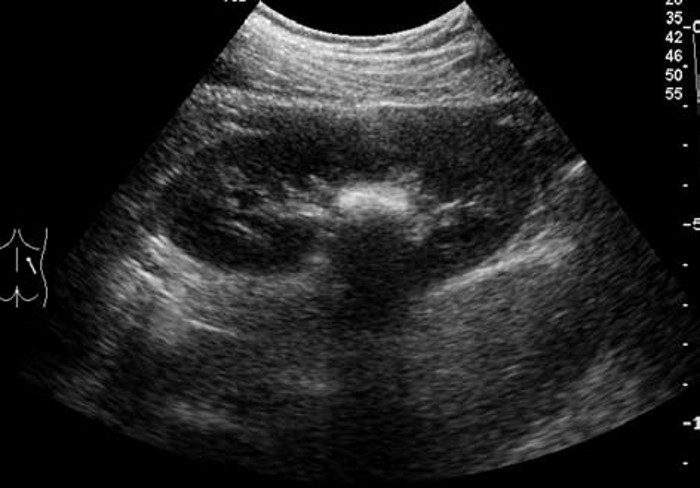

3. 鹿角状结石:大而分叉,形态不规则,超声往往仅显示局部突起的表面,呈几个孤立的强光团或弧形强回声带,像多个结石,但连续扫查可出现互相连续的一体。